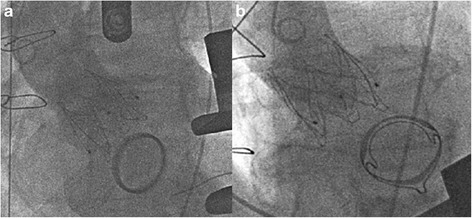

The cases were discussed by our multidisciplinary team of interventional cardiologists and cardiac surgeons as recommended [7] and after considering preoperative diagnostics and all available treatment options, a transapical approach for transcatheter aortic valve implantation was favored. The annulus size of the aortic valve as well as the optimal angulation was determined preoperatively with gated CTA (Computed Tomography Angiography). The procedure was performed in general anesthesia in a fully equipped hybrid operating room as described previously [8]. An anterolateral approach via the 5th intercostal space was used for exposure of the apex. Rapid pacing was applied for balloon aortic valvuloplasty with a 22 mm balloon (NuCLEUS™, pfm medical AG, Cologne, Germany). A self-expandable prosthesis (27 mm JenaValve™, JenaValve Technology GmbH, Munich, Germany) was implanted in typical manner after positioning with optimal angulation without rapid pacing or hemodynamic instability. Neither transesophageal echocardiography nor aortography identified a para- or transvalvular regurgitation in both cases (Fig. 1a, b). The patients were either extubated in the operating room or shortly after being transferred to the intensive care unit for further monitoring. Patient one was discharged on the 11th postoperative day (POD), patient two on POD 14. Follow up examinations (before discharge, in the rehabilitation facility and 2.8 or 1.3 years postoperatively, respectively) were performed and both patients presented with dyspnea according to NYHA II without echocardiographic evidence of paravalvular leakage at each point in time (Table 2). In the last examination, mean transaortic pressure gradient was 17 and 18 mmHg, respectively.

Fig. 1.

TAVI in a patient with a mechanical mitral valve prosthesis and b biological mitral valve prosthesis